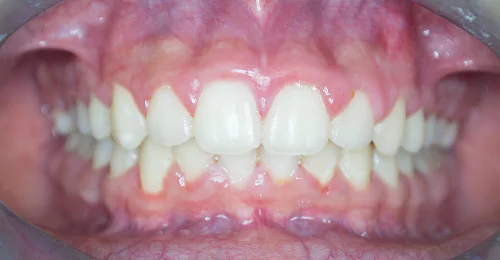

Anterior Crossbite Correction

A young newly married female had crossbite in front teeth and when she smiled she felt her teeth appeared crooked. Being newly married she also had concerns regarding wearing braces. Assessing the situation, we advised ceramic braces and treated the condition without extracting or removing any teeth.

Pre Treatment

The treatment was completed successfully after a period of 18 months. Our patient is now embarked on her newly married life with more confidence.